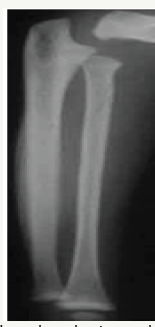

Complete healing and restoration of normal structures occurs in nutritional rickets. However distortion/sclerosis of spongiosa in affected segment may occur after healing & may remain visible for several years. Cortical thickening of segments of bone involved during active stage also may persist. Angular deformities secondary to pathological fractures result in deformities like knock-knee, bow leg and sabre shin (Figure 5).

Figure 5: Healing rickets bowing of the tibiae.